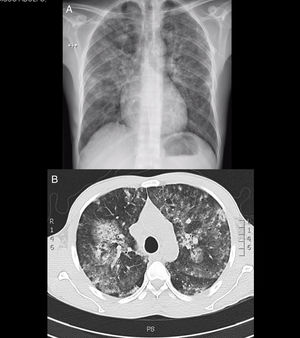

Tenía anemia grave, disfunción renal y opacidades mixtas en ambos campos pulmonares (fig. 1 y tabla 1). Se diagnosticó como síndrome pulmón-riñón y se inició tratamiento con altas dosis de esteroides y transfusión de glóbulos rojos. Inicialmente se consideró el diagnóstico de lupus eritematoso sistémico (LES) por el hallazgo de hipocomplementemia. En estudios adicionales se encontró positividad de múltiples anticuerpos: ANCA (antimieloperoxidasa y antiproteinasa-3), ANA, anti-Ro, anti-La, anticoagulante lúpico, factor reumatoide y anticardiolipina IgM. Los anticuerpos anti-Sm, anti-DNA y anti-membrana basal glomerular fueron negativos.

En una biopsia renal se observó glomerulonefritis endocapilar difusa con depósito de complejos inmunes y nefritis tubulointersticial. Una fibrobroncoscopia confirmó hemorragia alveolar (hemosiderófagos 40%) y descartó infección. Durante una evaluación posterior se observó perforación del tabique nasal y se confirmó con el paciente consumo frecuente de cocaína. Además de insistir en el cese del consumo se continuó tratamiento con prednisolona con buena respuesta clínica y ascenso de hemoglobina, pero con mejoría parcial de la función renal, por lo cual se adicionaron bolos mensuales de ciclofosfamida.